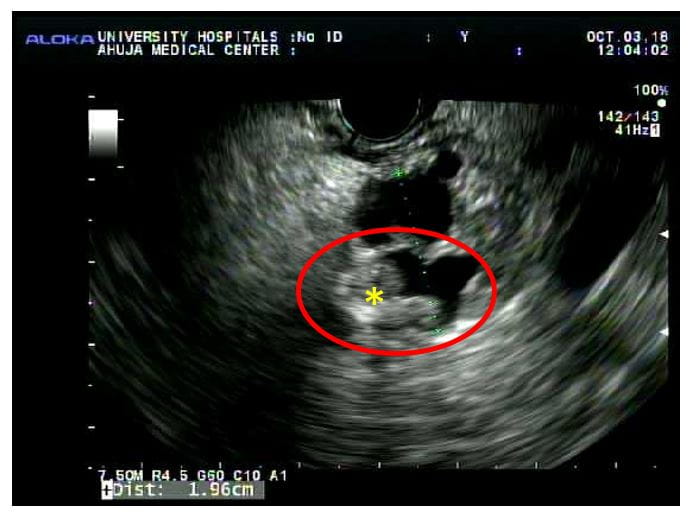

Pictured: a 56-year-old man who had a whipple for an intraductal papillary mucinous tumor with a solid nodule. He went home five days after the whipple with no complications.According to the UH algorithm, healthy patients with a long life expectancy (in light of an estimated 8 percent risk of pancreatic cancer at 10 years in cysts that are around 1.5 cm in size) are strong candidates for surgery. “We don't want to perform unnecessary surgery, but we don't want to leave in a potentially cancerous cyst,” Dr. Winter says.